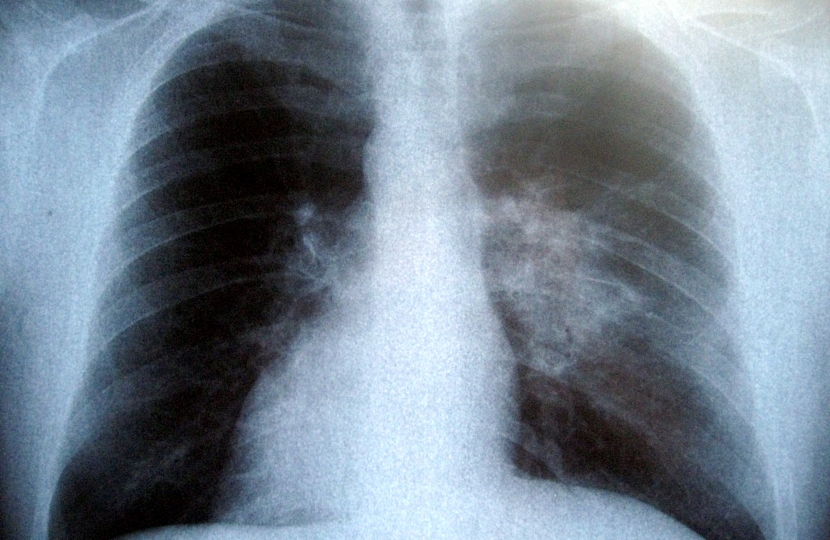

North Wales Assembly Member Mark Isherwood is encouraging his constituents to “listen to your lungs” by taking part in the British Lung Foundation’s online ‘breath test’.

The charity was showcasing their Listen to your lungs campaign, aiming to raise awareness that feeling out of breath doing everyday tasks could be a sign of lung disease.

“We’re throwing the spotlight on breathlessness, which can be a sign of lung disease, because fewer than half of us would be concerned at feeling short of breath doing daily tasks. Often people put it down to age or fitness, and don’t seek advice from their GP.